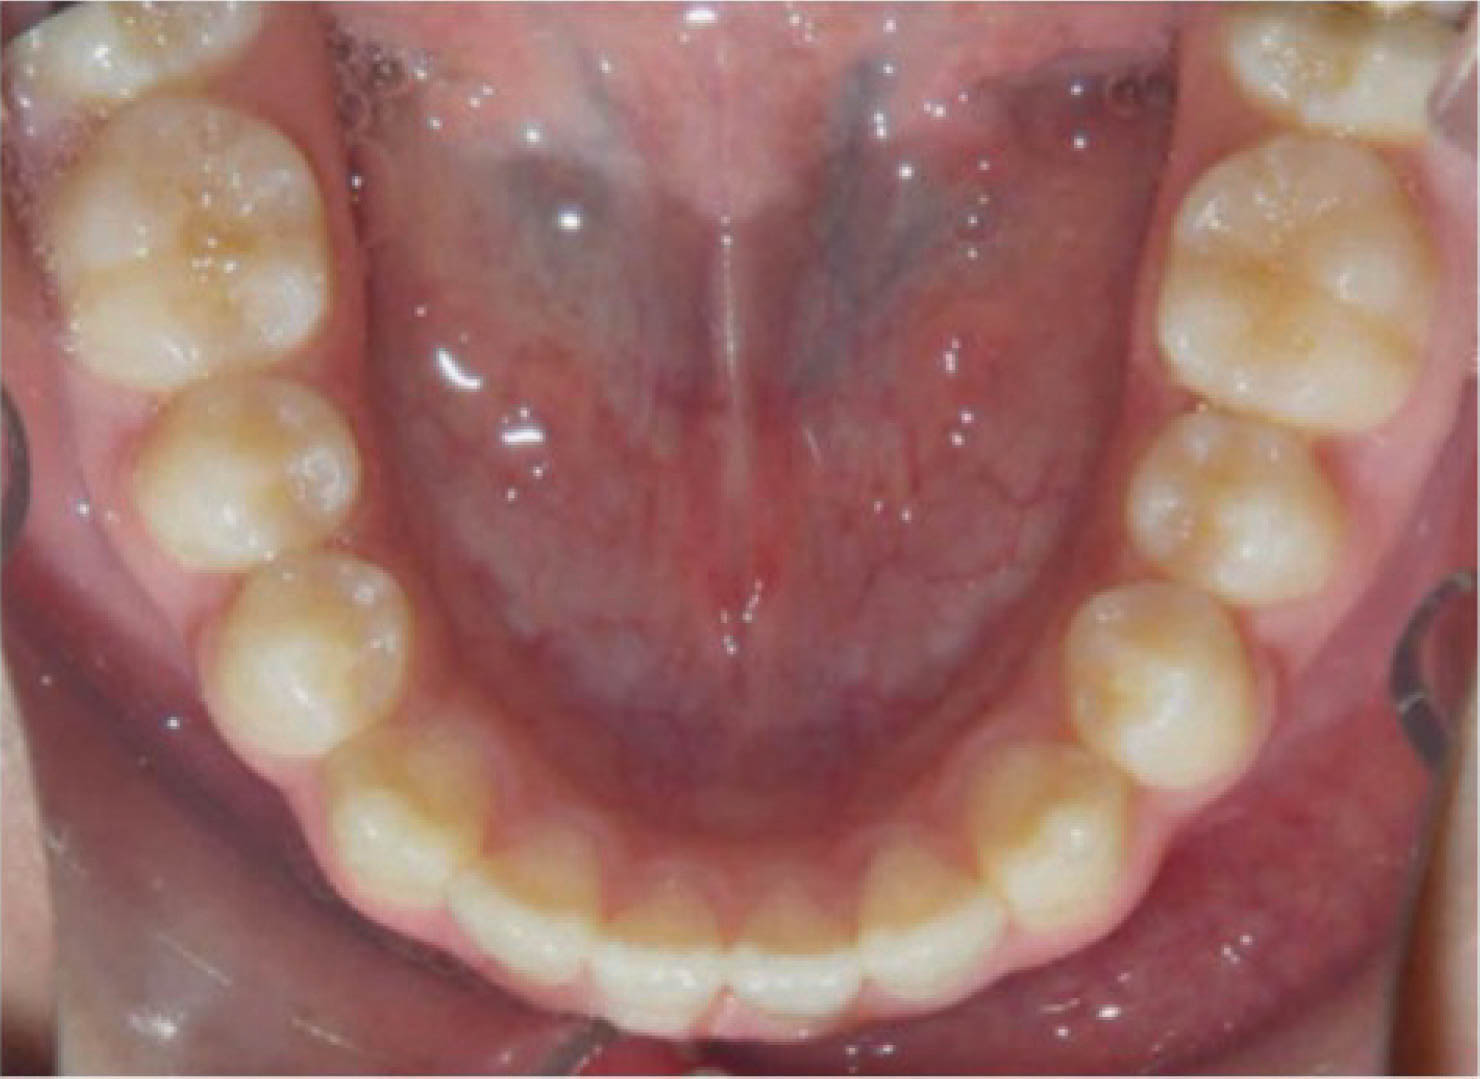

در بیمارانی که انسیزورهای بیرون زده با فضای بین دندانی دارند و آنها را به عقب میبریم احتمال تیپ شدن دندانها حتماً وجود دارد (شکل 41-6 و 42-6).

شکل 41-6